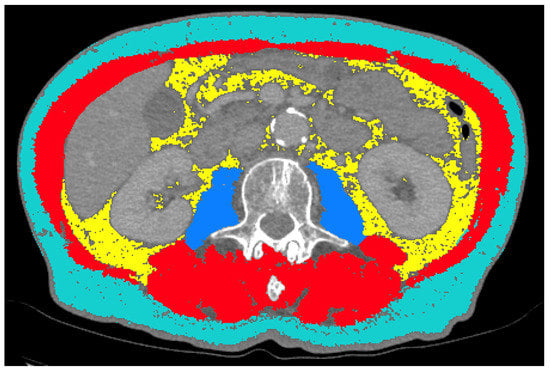

2.3. CT Body Composition Analysis

2.4. Statistical Analysis